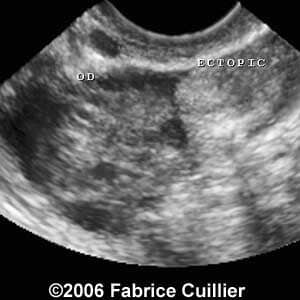

These are some cases of ectopic pregnancy (GEU) using the 2D and 3D scans.

Case 2